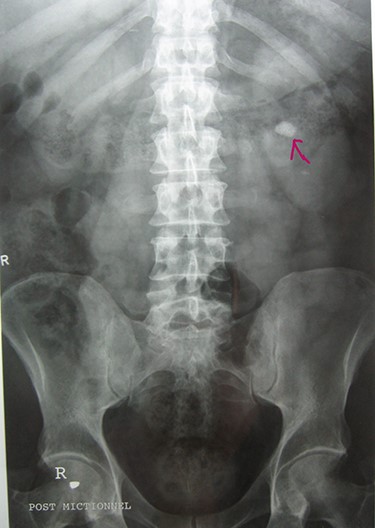

A 72-year-old man with a history of controlled diabetes and hypertension presented to our department with right inguinal swelling and intermittent lower urinary tract symptoms (LUTS) with pollakiuria, dysuria, prolonged micturition time and a sensation of a full bladder after micturition. He reported nausea, vomiting and right lower quadrant paint. The patient also reported having to manually compress the scrotum in order to empty the bladder. Physical examination revealed a slightly painful on palpation and reducible 6 cm right inguinal hernia extending into the right hemiscrotum. The body mass index of the patient was 31.4 kg/m2. His PSA was 4.3 ng/ml. On uroflowmetry, maximum flow rate (Qmax) was 13 ml/s and the voided volume was 180 cc. The uroflow curve was flat. The Bacteriological examination of urine was negative. Retrograde urethrocystography revealed right inguinal hernia containing a portion of the urinary bladder (Figs 1,2). He also had an intravenous urography in order to study the upper urinary tract and to have an idea of the renal function. This radiological exploration confirms the data of the retrograde urethrocystography and illustrates well the bladder hernia. However, a moderate left hydronephrosis with a nonobstructive pyelic calculus of 1.5 cm was observed on intravenous urography (Figs 3,4). Intraoperative findings revealed a direct right inguinal hernia with complete herniation of bladder into the scrotum. The bladder appeared healthy with no signs of injury and was restored to its normal anatomical position without resection. The hernia was repaired with a biologic mesh by the Lichtenstein technique. The patient had an uneventful postoperative course. Concerning his pyelic calculus problem, shock wave lithotripsy sessions were scheduled.

Intravenous urography: moderate left hydronephrosis and bladder addition image.

Intravenous urography: nonobstructive pyelic calculus of 1.5 cm.